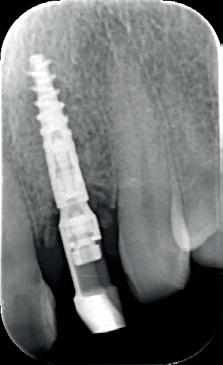

5. Implantaten geplaatst op geleide van een boorsjabloon; botopbouw met sinuslift volgens de GBR-techniek en Caldwell Luc methode; materialen: Oragraft & BioOss, Ossix membr, hyaluronzuur. In de BK is gekozen voor Bego implantaten (Bego SC en RSX 3,75x 11,5 & 13mm).

6. In het front zijn Bego 3,25mm

implantaten geplaatst terwijl in de zijdelingse delen voor een bredere diameter (3,75 & 4,1) is gekozen, met lengte 8,5 en 10mm.

7. OPT na abutmentchirurgie 6 maanden later. De integratie van de implantaten met de botopbouw & sinusliften verloopt voorspoedig.